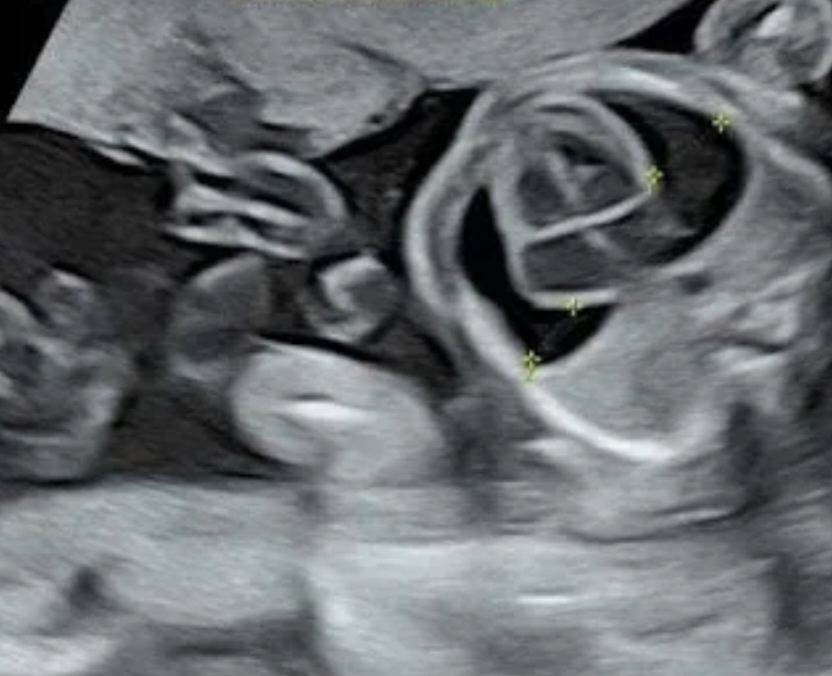

ഓമശ്ശേരി : ഓമശ്ശേരി ശാന്തി ഹോസ്പിറ്റലിൽ അഞ്ചു മാസം പ്രായമായ ഗർഭസ്ഥ ശിശുവിന്റെ ഹൃദയത്തിന് ചുറ്റും ഉണ്ടായിരുന്ന നീർക്കെട്ട് ഫീറ്റൽ മെഡിസിൻ ഡോ. പോൾ ചെതലന്റെ നേതൃത്വത്തിൽ "പെരികാർഡിയോസിൻഡസിസ് " പ്രക്രിയയിലൂടെ നീക്കം ചെയ്തു.

5ആം മാസത്തെ അനോമലി സ്കാനിനിംഗ് നടത്തിയപ്പോഴാണ് ഗർഭസ്ഥ ശിശുവിന്റെ ഹൃദയത്തിന് ചുറ്റും നീർക്കെട്ട് ഉള്ളതായും,അത് മൂലം ശ്വാസകോശം ചുരുങ്ങി ഇരിക്കുന്നതായും കണ്ടെത്തിയത്.

ഗർഭസ്ഥ ശിശുവിന്റെ മരണത്തിനു വരെ കാരണമായേക്കാവുന്ന ഈ അവസ്ഥയെ മാതാപിതാക്കളെ പറഞ്ഞു മനസ്സിലാക്കുകയും അവരുടെ സമ്മതത്തോടുകൂടി കൂടി ഗർഭസ്ഥ ശിശുവിനെ ഗർഭപാത്രത്തിൽ വച്ച് ഇഞ്ചക്ഷൻ നൽകി മയക്കി ഹൃദയത്തിന് ചുറ്റുമുള്ള നീര് വലിച്ചെടുക്കുകയും ചെയ്തു. രണ്ടു ദിവസത്തിനു ശേഷമുള്ള തുടർ സ്കാനിംഗിൽ ഹൃദയത്തിന് ചുറ്റുമുള്ള നീർക്കെട്ട് ഇല്ലാതാക്കുകയും, ശ്വാസകോശം പൂർണ വികാസം പ്രാപിക്കുകയും ചെയ്തതായി കണ്ടു.